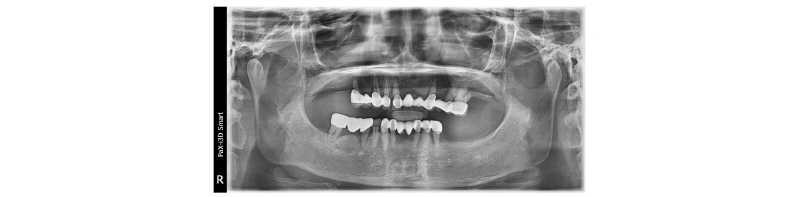

본 60세 여환은 윗니와 양쪽 아래 어금니들이 흔들리고 씹을 때 아프다는 주소로 본원에 내원하여 임상 및 방사선학적 검진 결과 아래와 같이 관찰되었다. #11, 15, 25, 26, 45, 47 치아는 Mob (++/+++) Per (+)와 bone loss, #12, 13, 23은 Per (+)와 root crack line이 관찰되었다. #16, 17, 27, 35, 36, 37 치아는 missing 상태였다. 이에 #11, 12, 13, 15, 23, 25, 26, 45, 47 치아는 hopeless teeth, #16, 17, 27, 35, 36, 37 치아는 missing teeth로 진단되었다(Fig. 1). #11, 12, 13, 15, 23, 24, 26, 45, 47 치아는 발치 후, short dental arch 개념으로 #i13, i14, i15, i23, i24, i25, i34, i35, i45, i46에 implant 식립 및 #i15 부위에 sinus lifting을 계획하였다. 발치 후, 상악은 완전 무치악, 하악은 양측 구치부 무치악이 되었고, 상, 하 rubber impression 채득 후, stone model 제작하였다. CBCT를 촬영 후 bone volume의 양을 계측하여 flapless implant surgery 및 immediate loading을 하기로 하였다. #45, 47 치아의 발치를 시작으로, #12 13 x 15 bridge와 #11 x x 23 x 25 26 bridge 제거 후, #11, 12, 13, 15, 23, 24, 26 치아를 발치하였다. 약 2개월간의 치유기간을 두고, CBCT 재촬영 및 bite 채득으로 vertical dimension 결정하였으며(Fig. 2, 3), 동시에 guided surgery를 준비하였다. 이때, guided surgery를 planning하기 위해서는 CBCT 영상(PHT-30LFO, VATECH)과 alveolar ridge와 soft tissue model을 scanning한 영상(TRIOS® 3, 3Shape, Fig. 4)이 하나로 합쳐진 가상의 영상을 이용하였다. #i13, i14, i23, i24, i25, i34, i35, i45, i46 위치에 implant fixture 식립과 customized abutment와 provisional bridge를 design하였다(Implant Studio®, 3Shape, Fig. 5). 이에 맞춰 3D printer (Projet® 3510HD, 3DSystems)로 surgical guide를(Fig. 6), milling machine (Arum 5X-200, DOOWON)으로 customized abutment와 provisional bridge를 제작하였다(Fig. 10). 임플란트 수술은 2회에 나눠서 시행하였다. 첫 번째 수술일에는 #i13, i14, i15, i23, i24, i25 fixture 식립과(Fig. 7-9) #i15에 lateral approach하여 sinus lifting과 bone graft (Bio-Oss Pen®, Geistlich)를 시행하였다(Fig. 11). 이와 더불어, #i15을 제외한 상악 implant fixture에 abutment 체결 후 provisional bridge를 교합조정하여 합착하였다. 1주일 후, 두 번째 수술일에는 #i34, i35, i45, i46 fixture 식립과(Fig. 9) 동시에 abutment 체결과 provisional bridge를 수복하였다(Fig. 12-16). 마지막 수술을 기점으로 4개월 후에 #i34, i35, i45, i46에 최종 인상 채득하여 도재금관 수복을 하였다(Fig. 17, 18). 향후 상악 임플란트에 대해 보철 예정이다.

Fig. 1. Panoramic view before treatment. |

Fig. 19. Panoramic view before treatment. |